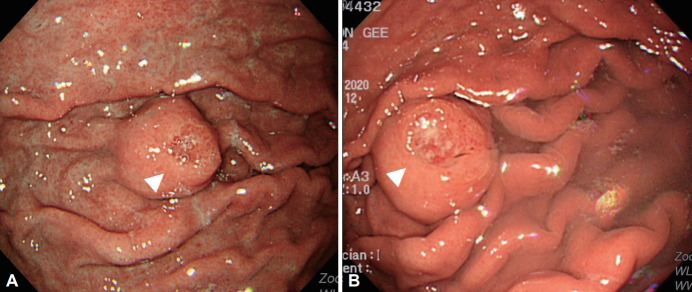

A Subepithelial Lesion of the Stomach Observed During Screening Endoscopy.

胃镜检查时发现胃上皮下病变。